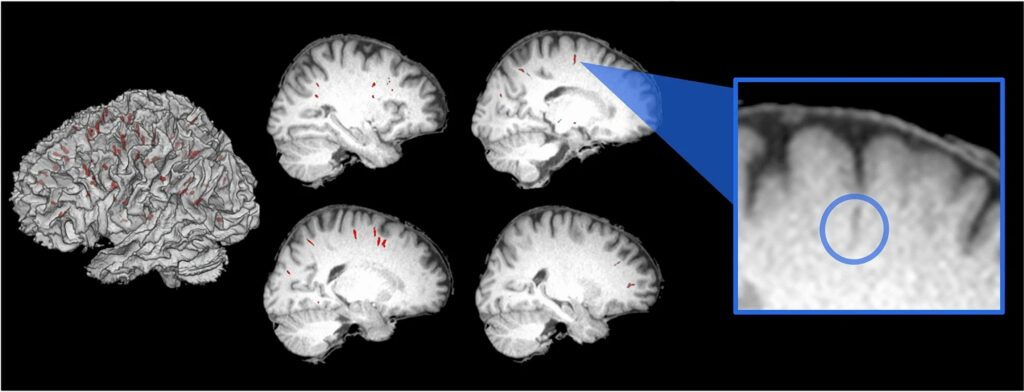

Cea mai recentă evaluare a efectului deformator al microgravitației asupra biologiei noastre se concentrează pe spațiile din jurul vaselor de sânge care trec prin creier, dezvăluind schimbări privind creierul astronauților care persistă și între misiuni.

Cercetătorii din SUA au comparat o serie de scanări prin rezonanță magnetică (RMN) ale creierului de la 15 astronauți efectuate înainte ca aceștia să petreacă 6 luni pe Stația Spațială Internațională și până la 6 luni după întoarcere.

Folosind algoritmi pentru a evalua cu…